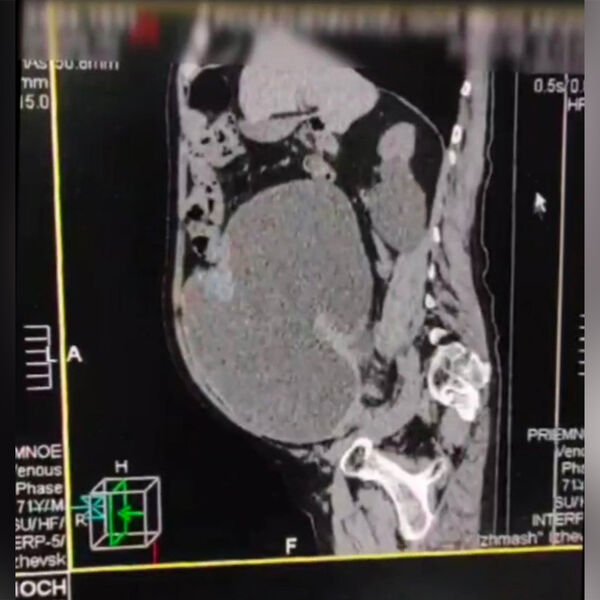

По словам врачей, из-за невнимательного отношения к своему здоровью у мужчины за несколько лет сформировался дивертикул мочевого пузыря (утолщение), в котором скапливалась моча. Мочевой пузырь разросся до таким объемов, что стал занимать большую часть брюшной полости.

«На фото виден переполненный мочевой пузырь, который занимает большую часть брюшной полости. После постановки уретрального катетера выведено 9 (!) литров мочи», — рассказали медики.